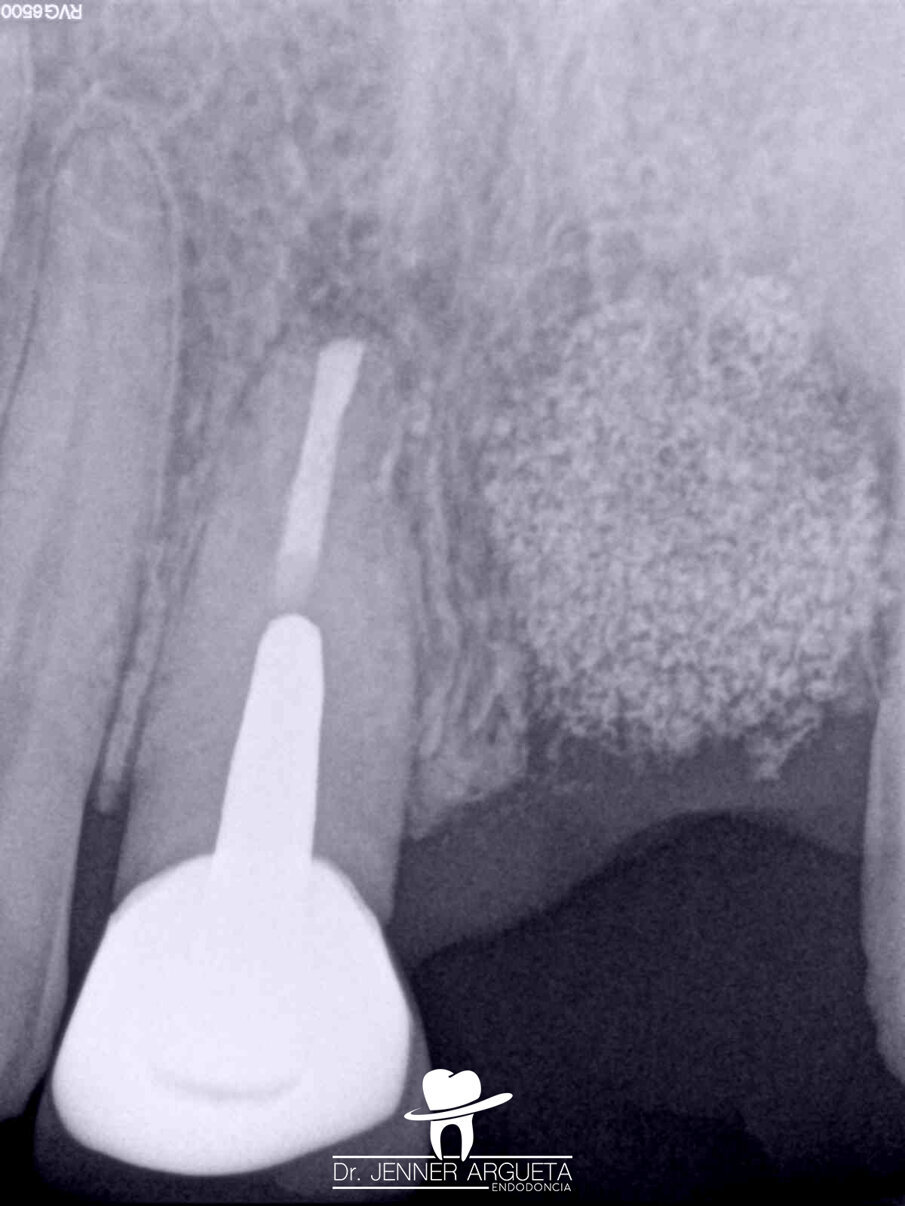

A 35-year-old male patient reported pain affecting the central incisors. Upon clinical examination, an acute periapical abscess was detected; radiographically, resorptive radicular defects in tooth #11 were observed. The patient reported a traumatic injury in the area several years before. The established diagnosis was pulp necrosis and an acute periapical abscess.

During the first appointment for root canal therapy, it was not possible to reach the complete length of the root canal, because the files tended to go inside of the mesial resorption. It was decided to seal the resorptive defect (Fig. 6a–c) using CeraSeal sonically activated using the EQ-S device (Meta Biomed; see video below).

At the second appointment, the material placed at the resorption was completely hard. That hard barrier allowed the file to pass through the entire length of the physiological root canal. The root canal therapy was finished using CeraSeal as the endodontic sealer (Fig. 7a–c). The three-year follow-up radiograph showed complete healing of the lateral radicular radiolucent area (Fig. 8a–c).

Figs. 6a–c: Radiographic sequence of the treatment performed in tooth #11. Initial radiograph. The root resorption and lateral radiolucent area were evident (a). Working length measurement at the level of the resorption (b). Root resorption repair with a calcium silicate-based material (c).

Figs. 7a–c: Radiographic sequence of the treatment performed in tooth #11. Initial radiograph. The root resorption and lateral radiolucent area were evident (a). Master cone fitting at the level of the complete working length (b). Completed root canal therapy (c).

Fig. 8: Radiographic sequence of the treatment performed in tooth #11. Initial radiograph. The root resorption and lateral radiolucent area were evident (a). Completed root canal therapy (b). Three-year follow-up radiograph showing complete healing of the lateral radicular radiolucent area and the correct sealing of the resorption (c).